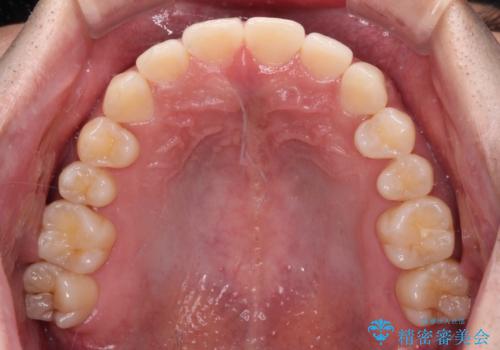

下顎前歯の叢生解消も提案しましたが、上顎の隙間が閉じたことで満足されました。

空隙歯列弓はマウスピースによる保定を行っても、すぐに後戻りを起こしてしまうため、ワイヤーリテーナーによる保定を併用することとしました。